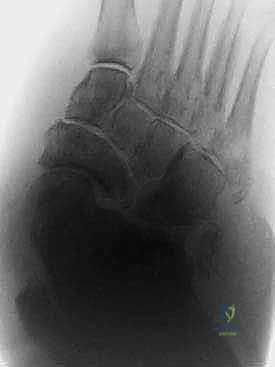

الخطوة الأولى: التخطيط الجراحي الدقيق

قبل دخول غرفة العمليات، يتم إجراء فحوصات شاملة تشمل الأشعة السينية، الأشعة المقطعية ثلاثية الأبعاد (3D CT Scan) لفهم خريطة العظام المتفتتة، وتقييم شامل للدورة الدموية (Doppler Ultrasound) لضمان وصول دم كافٍ لالتئام الجروح.

الخطوة الرابعة: إعادة بناء وتثبيت المفاصل (Arthrodesis)

هذه هي المرحلة الأهم، حيث يتم دمج العظام المتضررة معاً لتكوين كتلة عظمية صلبة ومستقرة. يعتمد الدكتور هطيف على تقنيتين رئيسيتين حسب حالة المريض: